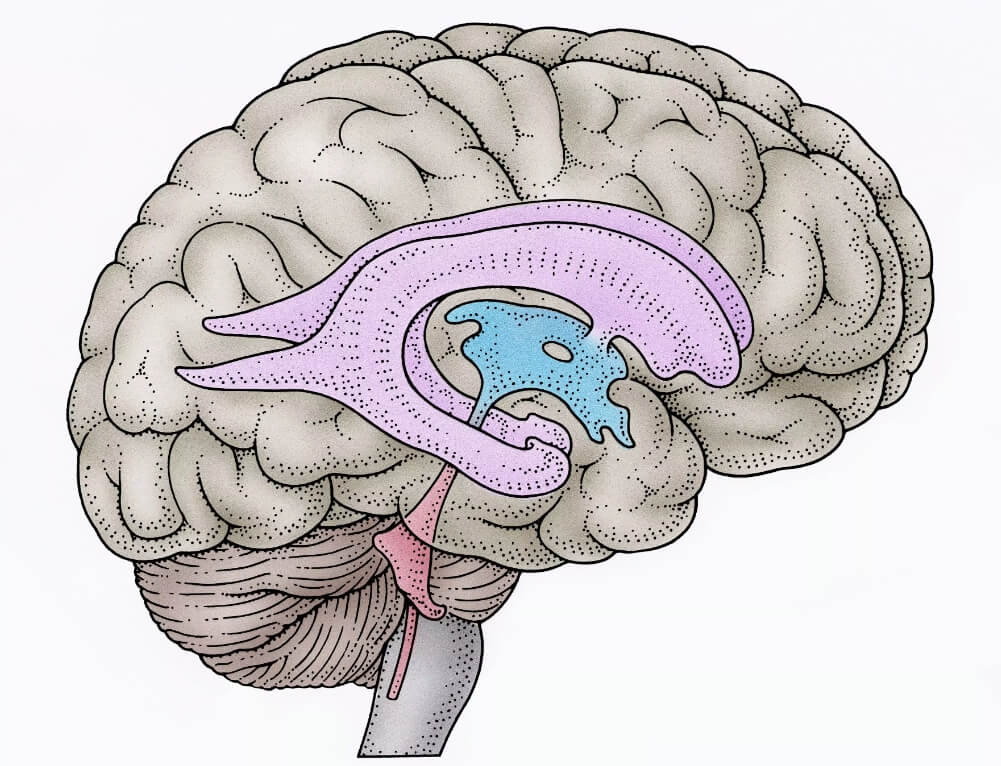

Легкие рисунки головного мозга: Пошаговые инструкции